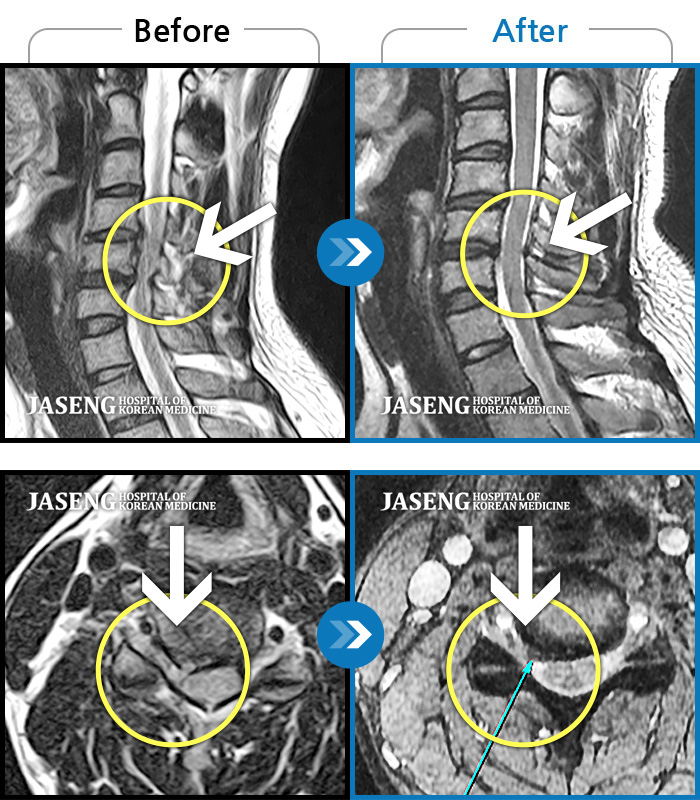

MRI 치료사례

목 통증 및 우측 팔 통증으로 위로 들 수 없는 상태